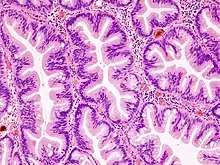

Ils sont définis morphologiquement comme des tumeurs épithéliales glandulaires polypoïdes sessiles, ou parfois planes, composées de glandes, ou « cryptes », ayant une architecture festonnée ou dentelée, avec aspect en festons ou « en dents de scie » créé par les indentations de l’épithélium bordant les cryptes. Ces lésions sont décrites dans la très grande majorité des cas dans le côlon et le rectum mais d’autres localisations digestives ont été décrites.